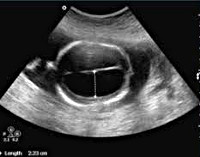

• Комбинированное гинекологическое УЗИ (ТА+ТВ). С помощью трансабдоминального датчика можно выявить аномалии развития, изменение формы матки, гиперпластические процессы в эндометрии, наличие и особенности расположения миоматозных узлов, других новообразований, патологию маточных труб и яичников, оценить проходимость цервикального канала. Для более детальной визуализации трансабдоминальное обследование дополняют трансвагинальным.